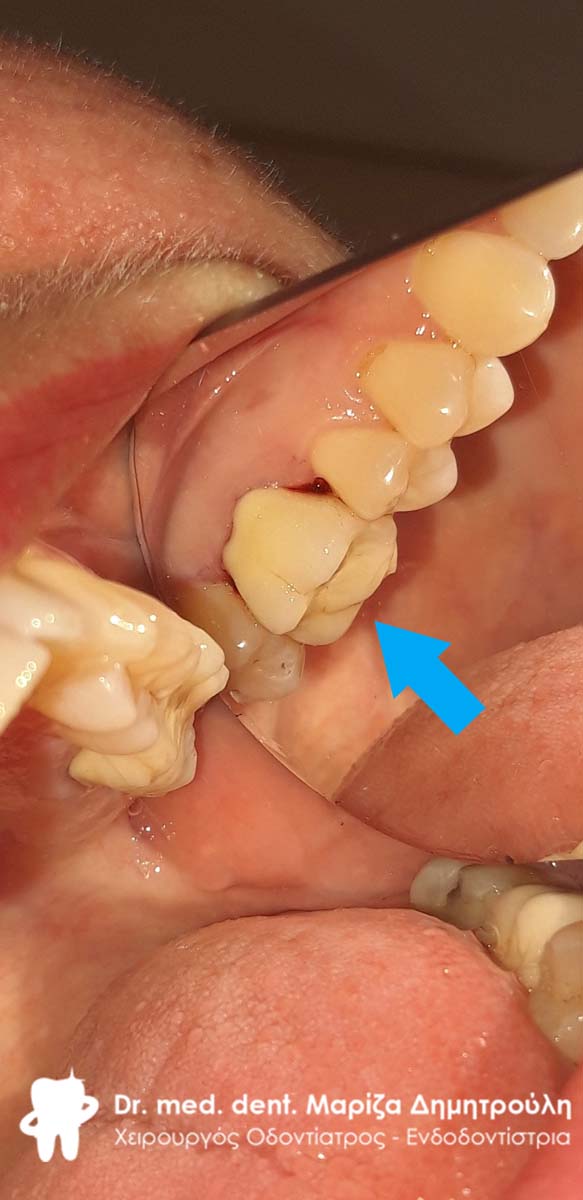

Τελική κλινική εικόνα του ολοκεραμικού επένθετου στο γομφίο